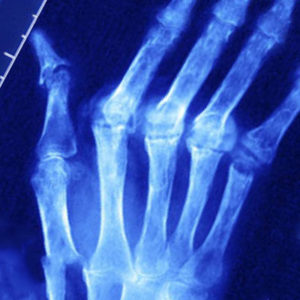

Диагностика псориатического артрита во многом основана на наличии ряда характерных рентгенологических признаков заболевания:

Рентгенография выявляет следующие свидетельства псориатического суставного артрита: